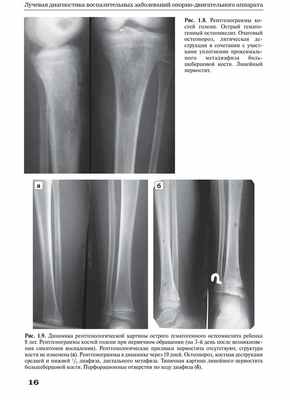

Основу диагностики хронического остеомиелита составляет рентгенгенография конечностей: утолщение кости, полости, секвестры, остеосклероз, сужение костно-мозгового канала, утолщение надкостницы. Важное место в диагностике свищевых форм занимает фистулография, томография, сцинтиграфия и другие методы диагностики.

Диагностика. На рентгенографии определяется остеопороз в области перелома, изъеденность концов кости, мелкие очаги деструкции с секвестрами (коралловидная перестройка кости). При послеоперационном остеомиелите рентгенологически определяется остеопороз вокруг металлической конструкций, очаги деструкции с секвестрами.